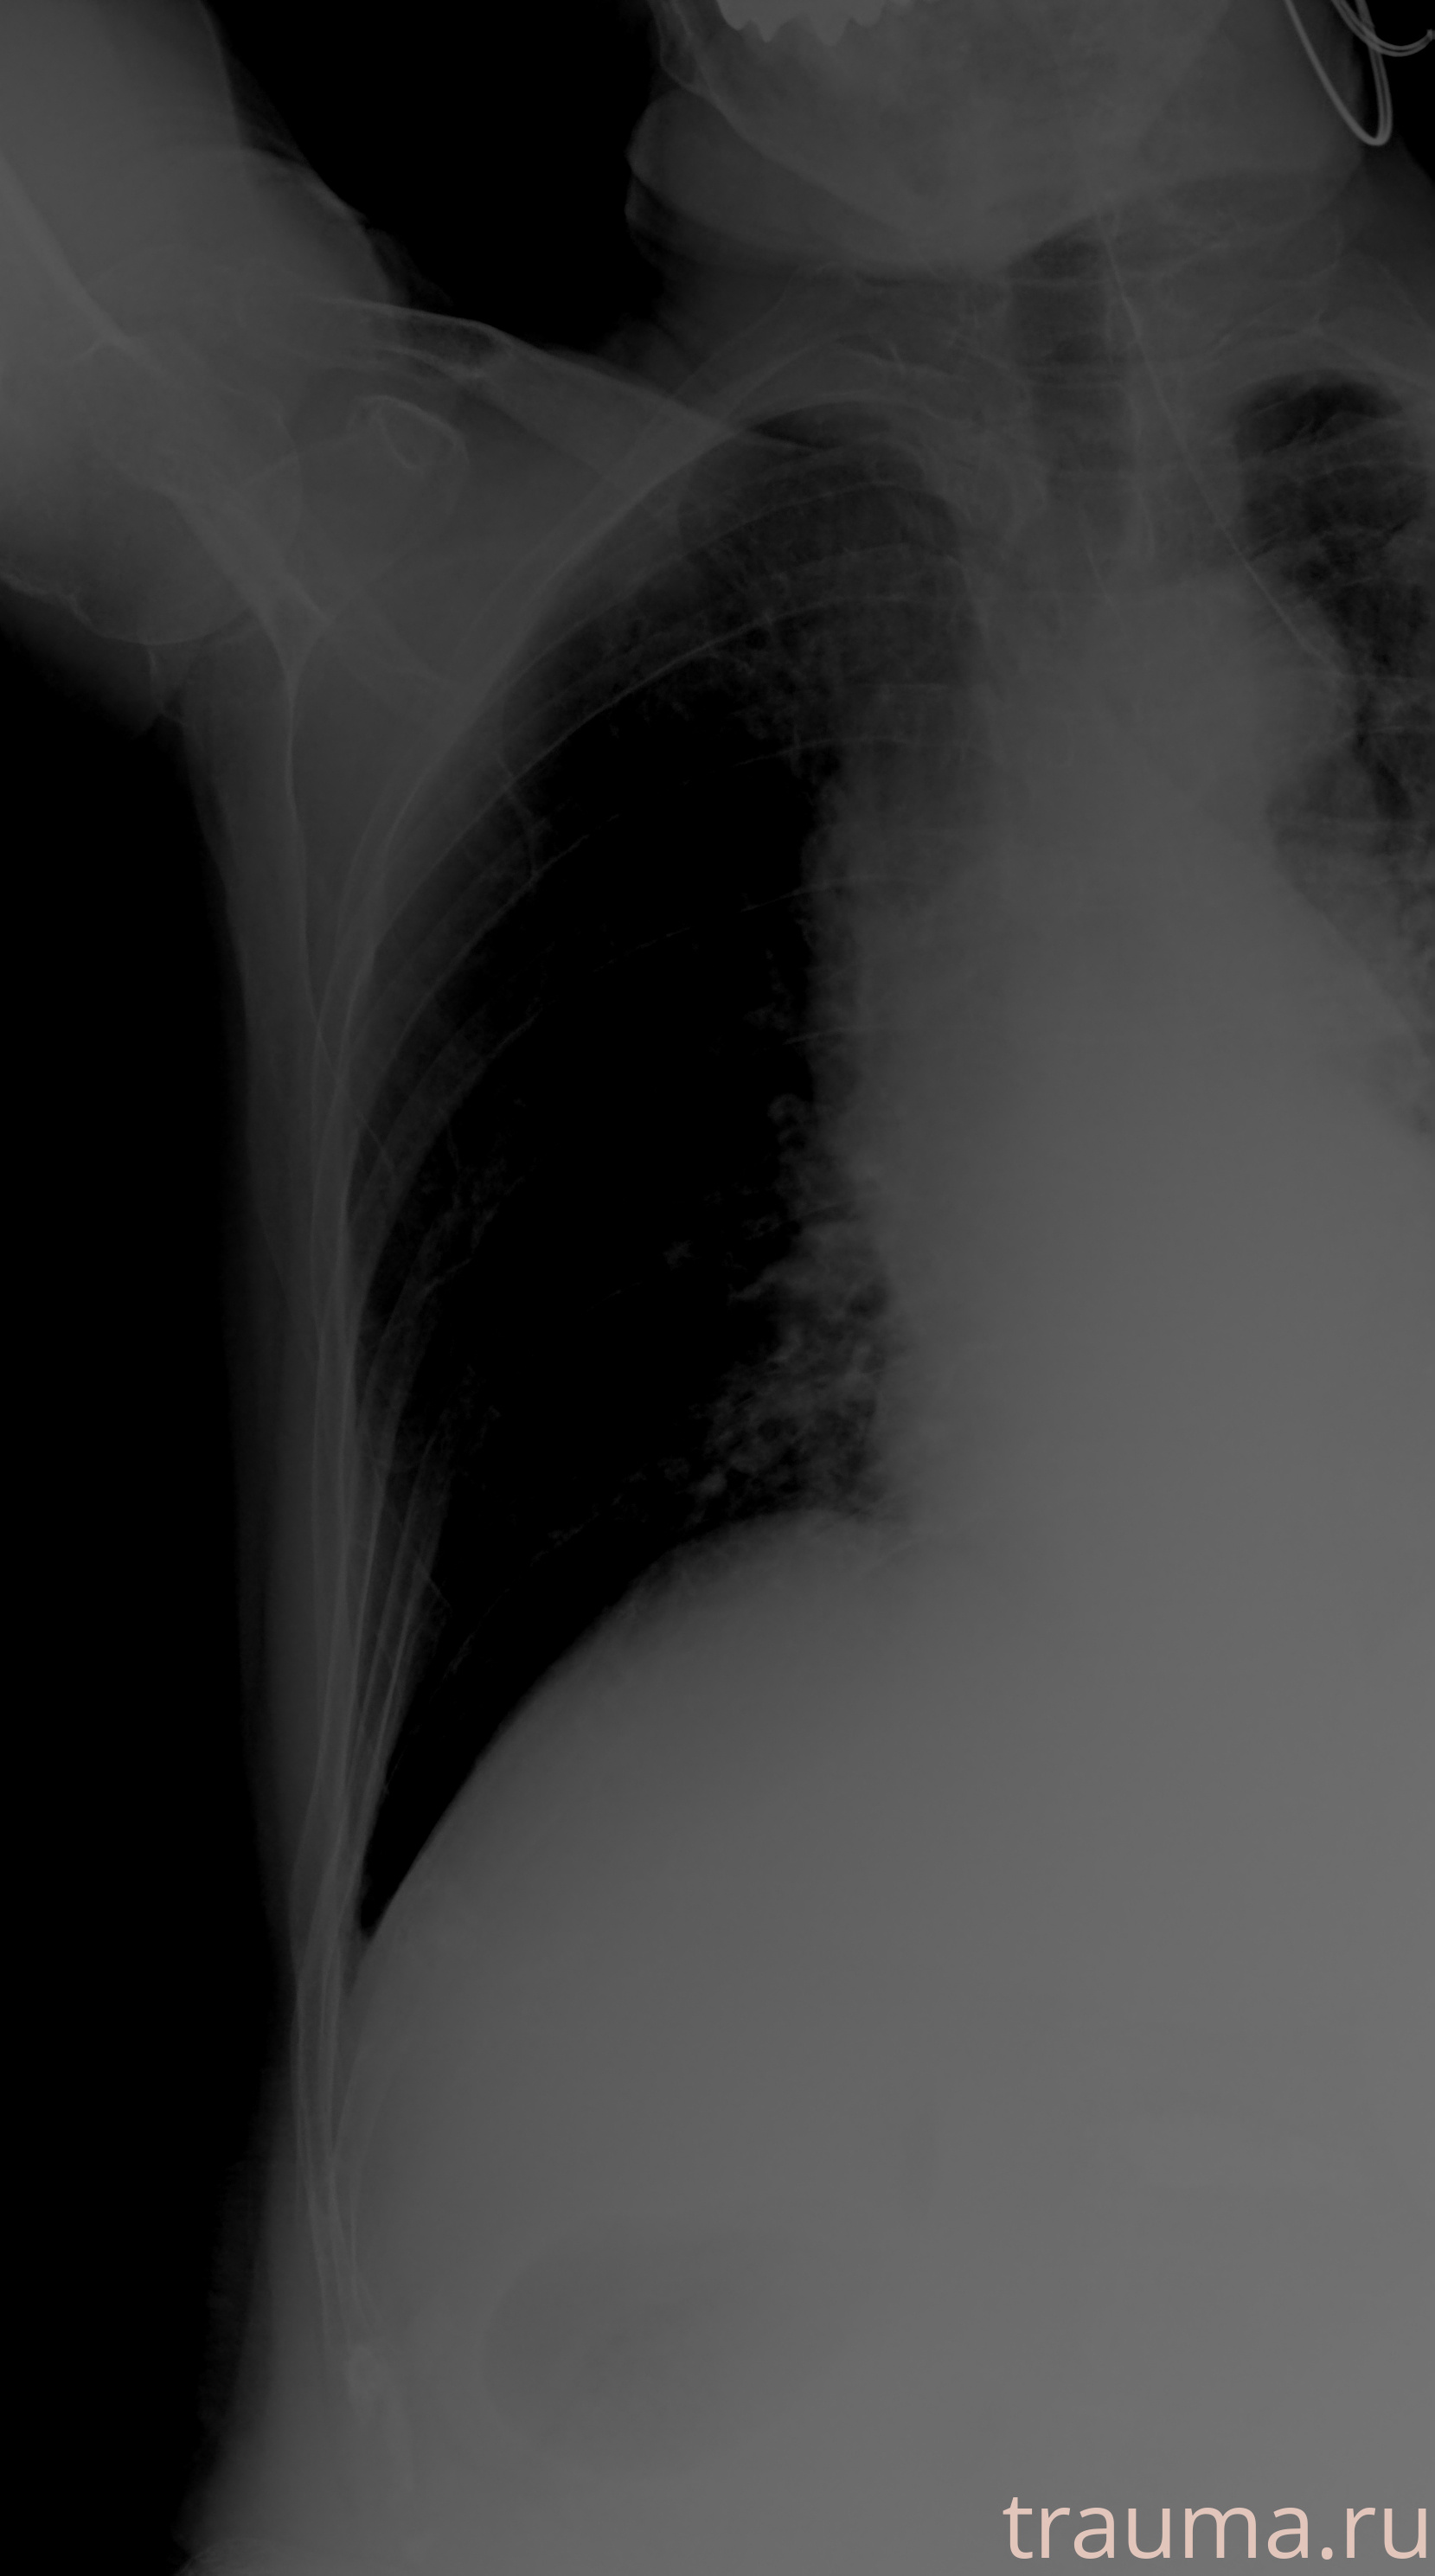

Рентген на дому: по вашему адресу приезжает врач-рентгенолог, травматолог-ортопед с мобильным рентгеновским аппаратом, проводит диагностику травмы или заболевания, делает необходимые рентгенограммы, дает рекомендации по дальнейшему лечению. Получить качественные снимки в домашних условиях возможно благодаря уникальной методике, разработанной МосРентген Центром для института  Склифосовского